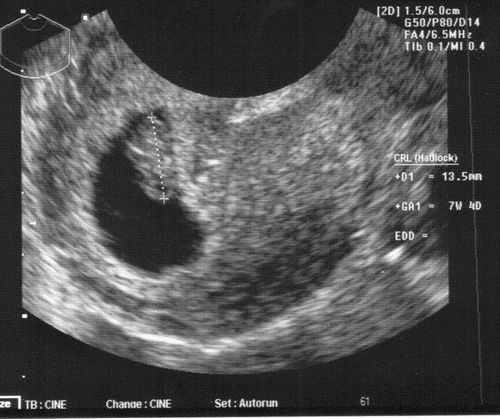

Фото малюка, УЗД

Сьомий тиждень вагітності - вдалий час для того, щоб стати на облік. Чим раніше ви це зробите, тим раніше пройдете необхідне обстеження і будете впевнені, що все в порядку. Вам будуть призначені аналізи крові, сечі, вимірювання артеріального тиску, росту, ваги і т.д. При необхідності лікар може призначити дослідження рівня гормонів крові, наприклад, ХГЧ на 7 тижні вагітності. Також вам випишуть направлення на ультразвукове дослідження. УЗД на 7 тижні вагітності проводиться тільки за показаннями, а скринінгове дослідження призначається на 11-14 тиждень.

Чому 7 акушерська тиждень вагітності відрізняється від гестаційної? Фактичним початком вагітності є день овуляції, коли відбулося запліднення яйцеклітини. Однак це у різних жінок відбувається в різні дні менструального циклу, тому справжнє початок вагітності визначити вкрай складно. Тому для зручності підрахунків і точності термін вагітності прийнято вважати від першого дня останньої менструації. Тому гестаційний термін відрізняється від акушерського приблизно на два тижні. Однак загальноприйнята саме акушерська система відліку, і завжди термін вагітності, нормативи розмірів малюка вказуються саме за цією системою. Дуже хочеться вже зробити УЗД і побачити малюка! Чи можна зробити фото плода під час УЗД?

Ультразвукове дослідження - це безпечна для плоду і матері діагностична методика, і вже в 7 тижнів цілком можна зробити УЗД. Однак на такому ранньому терміні малюк ще дуже маленький, тому фото, на якому помітні риси обличчя, положення, ручки, ніжки малюка, зробити ще не вийде. Перше УЗД призначається на 11-14 тиждень вагітності. На цьому терміні вже можна виключити аномалії розвитку, генетичну патологію малюка, а на фото при УЗД буде все добре видно. Тому краще трохи почекати. Що робити, якщо болить живіт на 7 тижні вагітності?